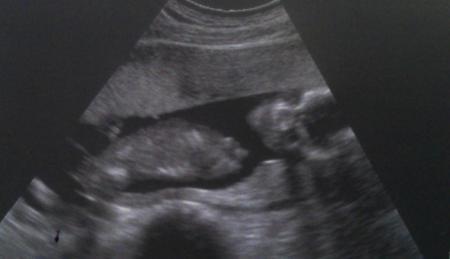

Bin erleichtert von meinem FA Besuch zurück. Hatte zum ersten Mal 4 Wochen warten müssen und war dadurch irgendwie noch schlimmer aufgeregt. Es wurde US gemacht und die Ärztin hat sich Zeit genommen. Die Tendenz für das Geschlecht ist... ...eine Püppi !!! Sah beim Ersttrimesterscreening auch schon danach aus. Jippieh!!! Aber generell ist uns das Geschlecht wurscht, Hauptsache gesund. Und wer weiß...vielleicht versteckt sich da ja auch noch ein Mikropenis ...bitte keine Rückschlüsse zum Kindsvater Muss aber zugeben, dass ich stark das Gefühl hatte, dass es ein Mädchen wird und deswegen spreche ich jetzt auch einfach mal von "ihr". Sie wiegt 200 g und ist echt aktiv gewesen. Hat sogar ihre Hände zwischen die Beine gelegt...eine echte Lady bedeckt sich eben, hihi. SSL wurde nicht mehr gemessen, aber Kopfdurchmesser, leider hab ich den Wert nicht. Aber es ist genau zeitgerecht entwickelt ...rechnerisch und von Entwicklung her genau 17+1. Genau im Standart zu liegen, tut doch auch mal gut. Bei mir sind die Eisenwerte und der Blutdruck nicht so toll, deswegen leierts mich eben so oft weg. Aber mit der Kleinen ist alles toll, deswegen steh ich das durch, genauso wie die Übelkeit, die bei mir irgendwie nicht weggehen will. Ich habe eine Hinterwandplazenta. Wisst ihr eigtl was häufiger ist? Hinterwand oder Vorderwand? Ist eines von beiden nachteiliger? Ich sende noch ein Bild mit. Ich finde es total lustig, weil sie direkt in die "Kamera" guckt und das sieht bissl gruselig aus durch die Augenhöhlen, wuhaaa. Ich finds trotzdem totaaaal süß. Ich hab sie schon so unheimlich lieb. Und falls Mikropenis und so, dann natürlich ihn Danke fürs Däumchendrücken, es hat geholfen